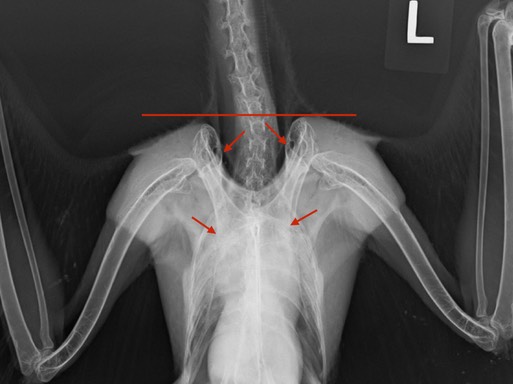

Cooper’s Hawks hunt other birds. If you feed songbirds in your yard, you may also attract a Cooper’s Hawk. A common cause of injury in Cooper’s Hawks is collision with a window, often while chasing prey. 21-014 flew into a window at a Kennewick Fire Station, injuring her right shoulder. If you look at the horizontal line in the radiograph below you will notice that the right shoulder is lightly lower than the left shoulder. The upper arrows are pointing at the top of the scapulas. The right scapula is lower than the left scapula. The bottom arrows are pointing at the base of the coracoids where they attach to the sternum. The right coracoid is dislocated and lower than the left coracoid.

Coracoid fractures and dislocations are a fairly common shoulder injury. There are currently five other birds recovering from coracoid injuries at BMW: another Cooper’s Hawk, a Red-tailed Hawk, a Barn Owl, a Great Horned Owl and a Bald Eagle.